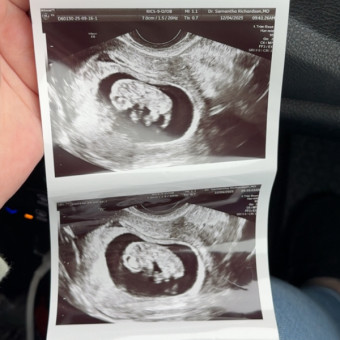

Baby T 🩵

Carly & George Tschappat

July 1, 2026